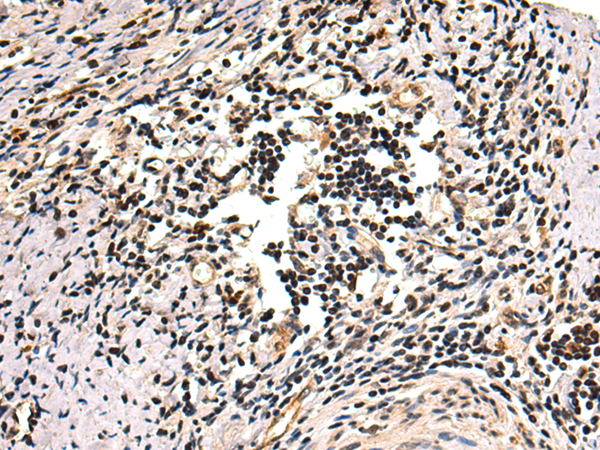

分类: 科研抗体货号: P00543别名: DUP; FAP4; MRP1应用: WB,IHC反应种属: Human, Mouse